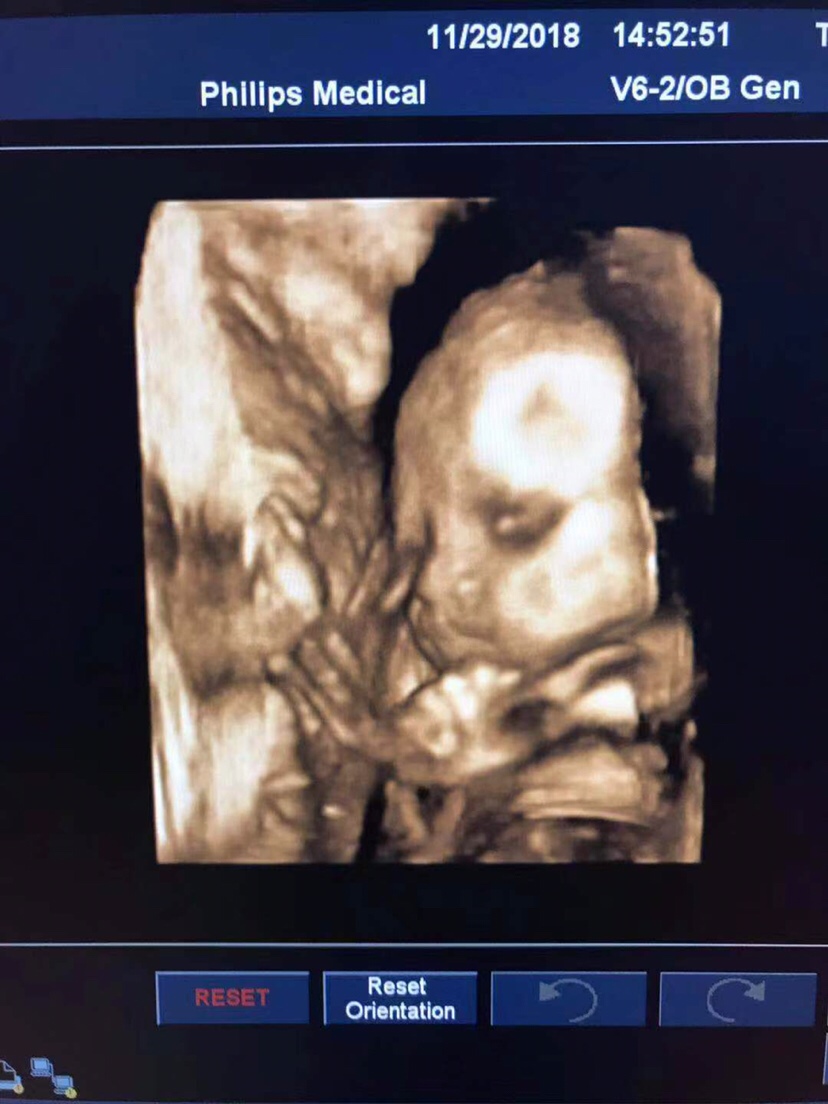

孕39周+6天

感觉像爸爸 哈哈哈

红瑶[帖主]:好吧哈哈